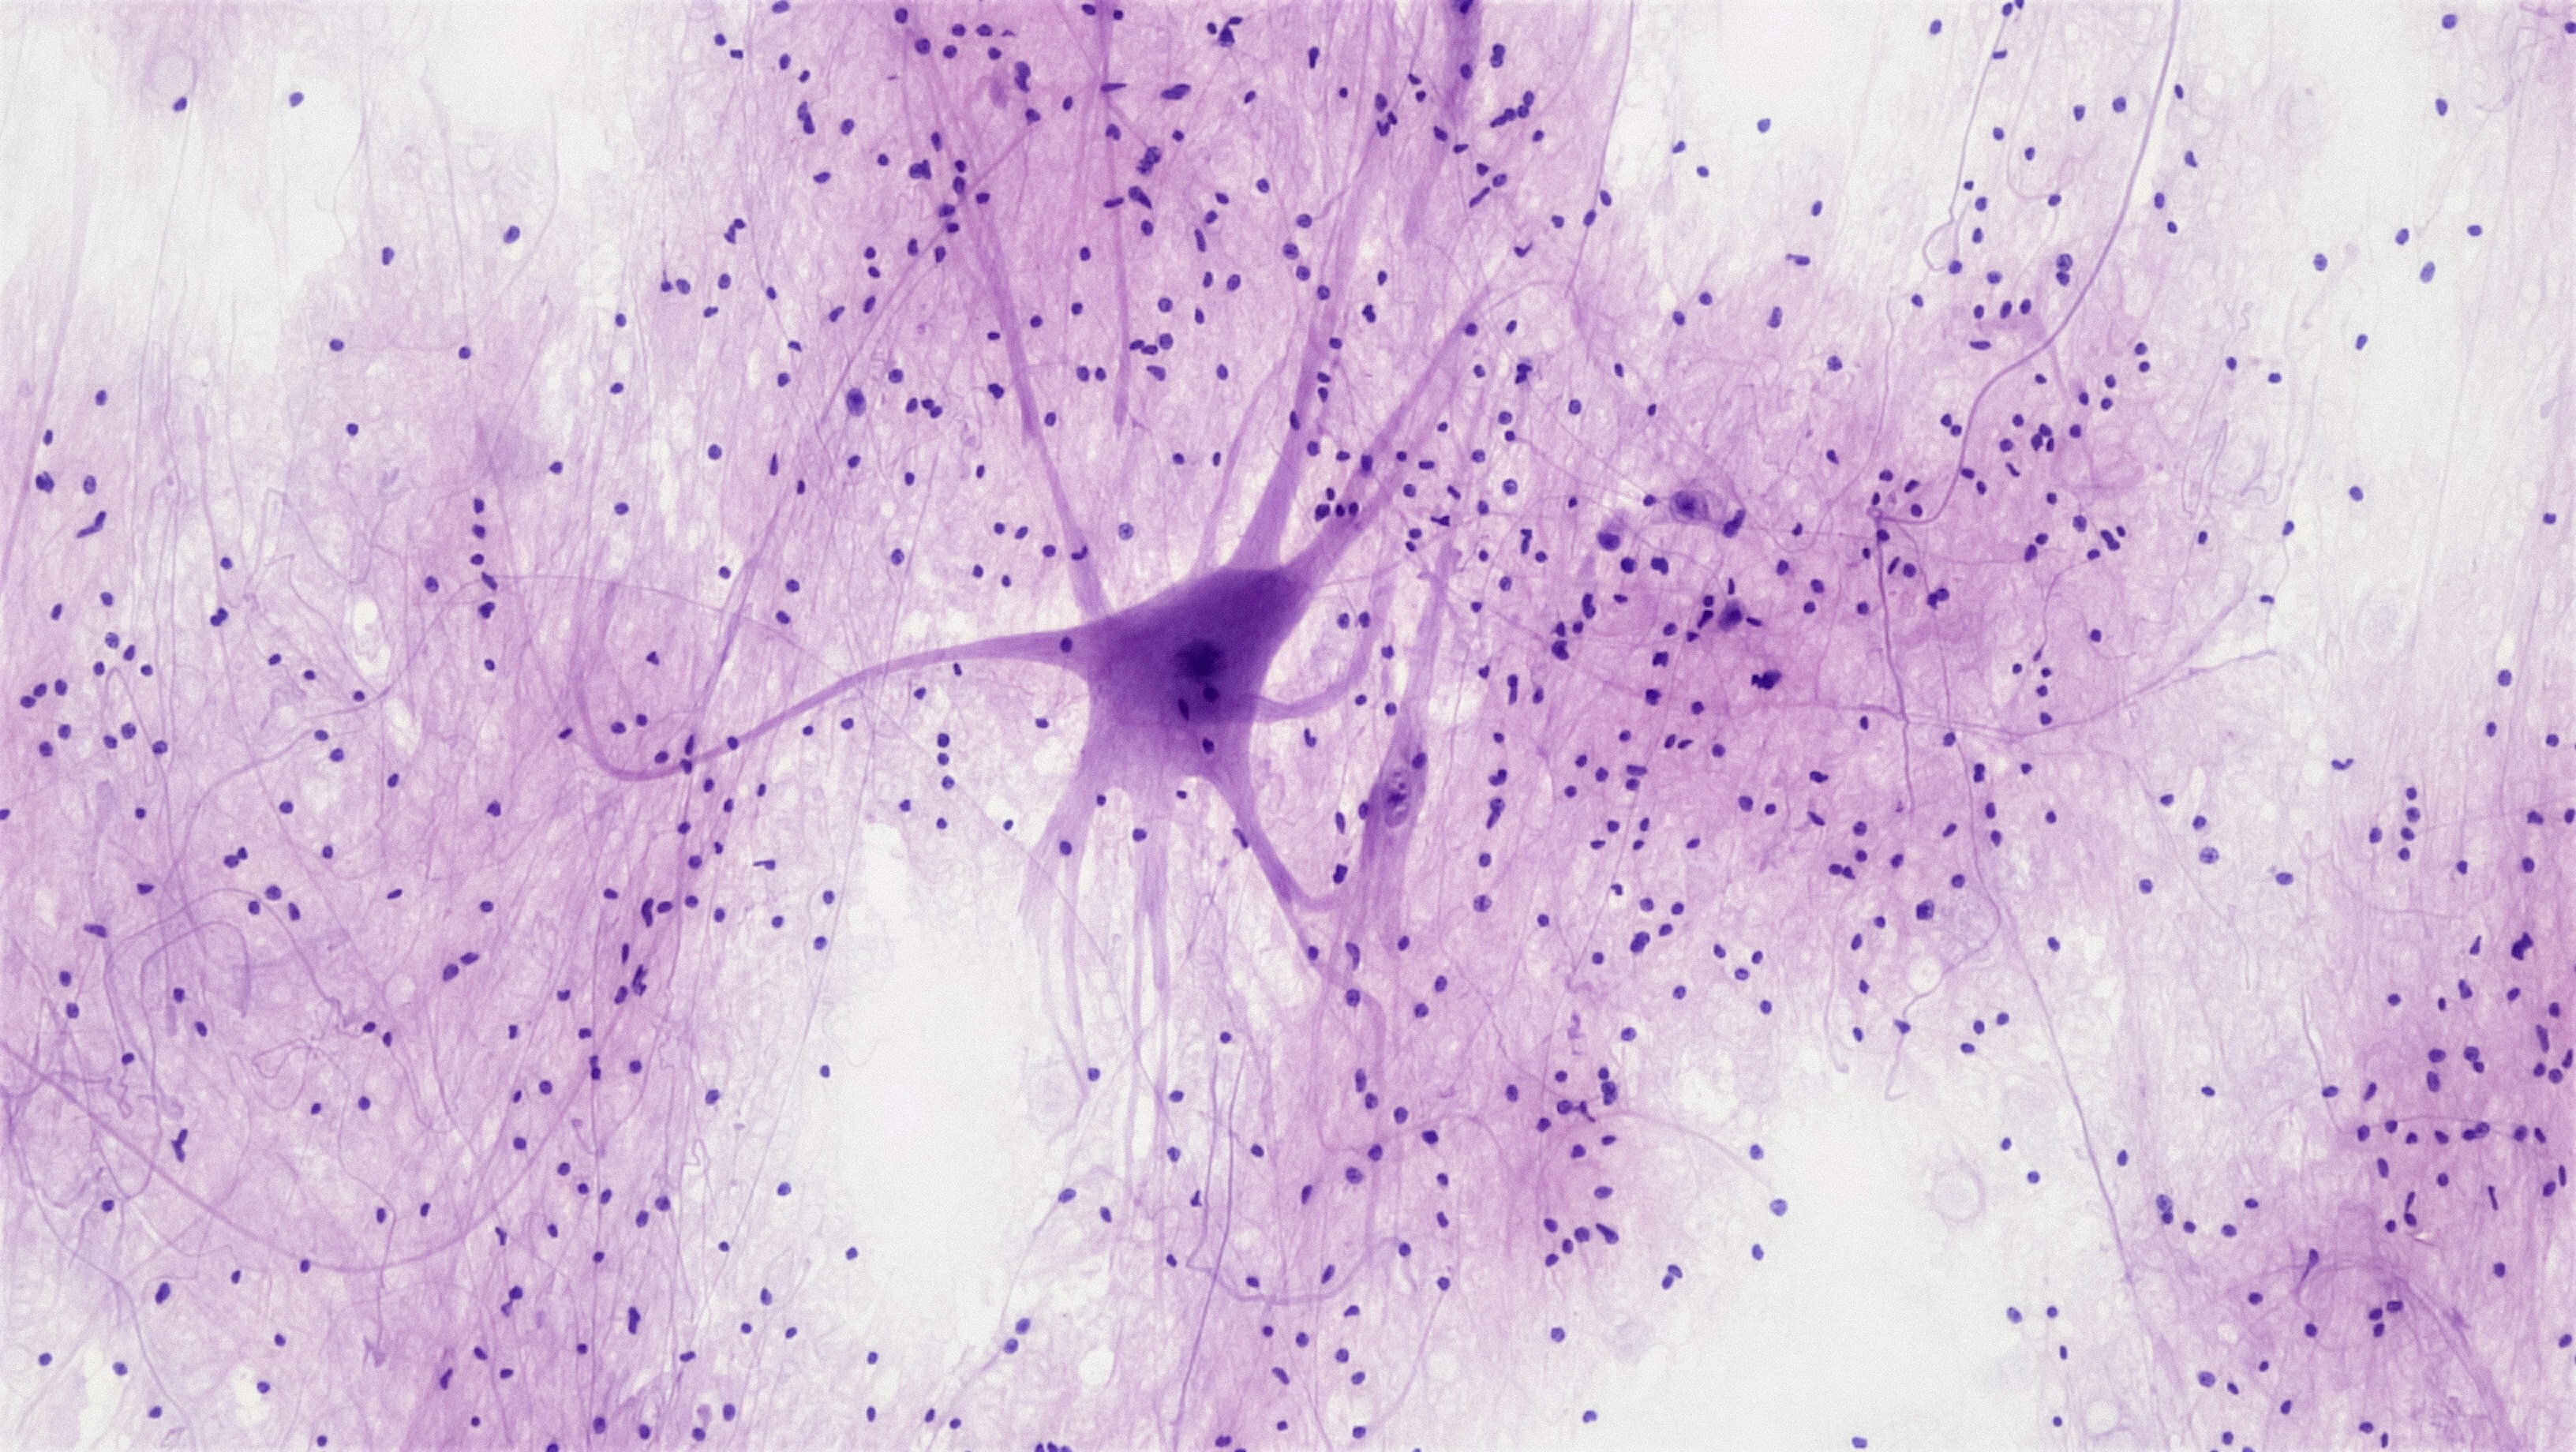

Учёные воссоздали гибкий синапс — «электрод», который передаёт информацию от глаза мозгу